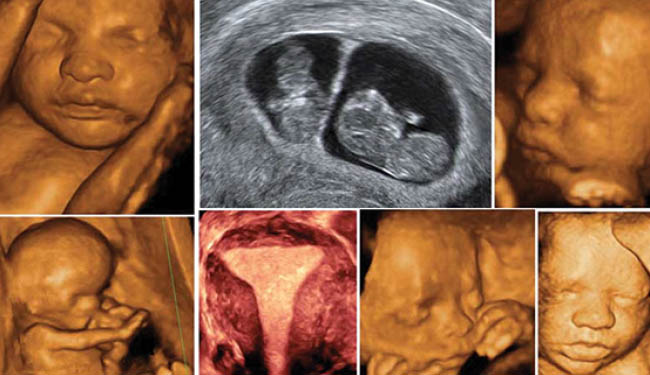

4 boyutlu ultrason hizmete girdi

Bingöl Kadın Doğum ve Çocuk Hastalıklar Hastanesi, sağlık alanında iyileştirme sağlayarak 4 boyutlu ultrason hizmeti vermeye başladı. Yapılan iyileştirilmeyle sevklerin önü kesilecek.